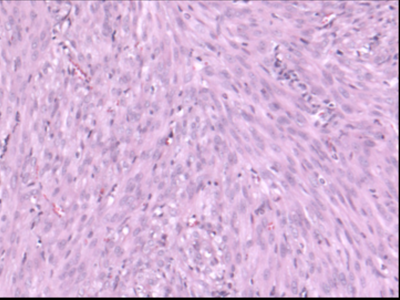

Histologic image of leiomyosarcoma

How can we better diagnose and treat leiomyosarcoma?

Leiomyosarcoma is a poorly understood sarcoma that arises from smooth muscle cells or their progenitors. Leiomyosarcoma presents diagnostic and therapeutic dilemmas, with multiple molecular subtypes and few common mutations or therapeutic targets between patients.

Our work focuses on developing liquid biopsies to detect copy number alterations seen in leiomyosarcoma, generating valid models of leiomyosarcoma to facilitate laboratory research, and identifying novel treatment strategies using patient-derived xenograft (PDX) models.